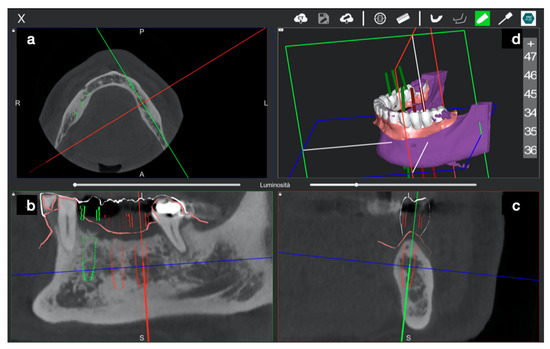

2.2.2. Trace

2.2.3. Place